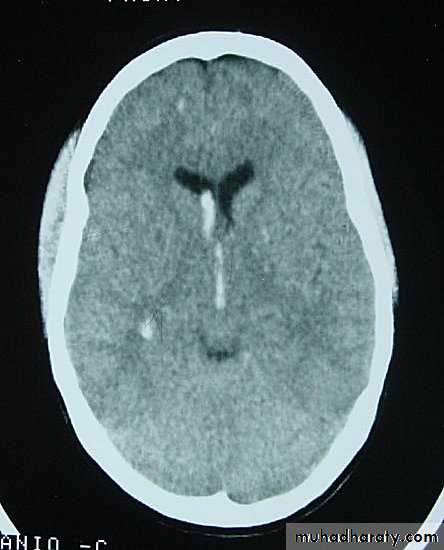

5. Hydrocephalus

a. Acutely due to obstruction of CSF outflow due to intraventricular blood.

b. Delayed post-traumatic communicating hydrocephalus due to impaired CSF reabsorption following traumatic subarachnoid haemorrhage

Intraventricular blood can lead to Hydrocephalus